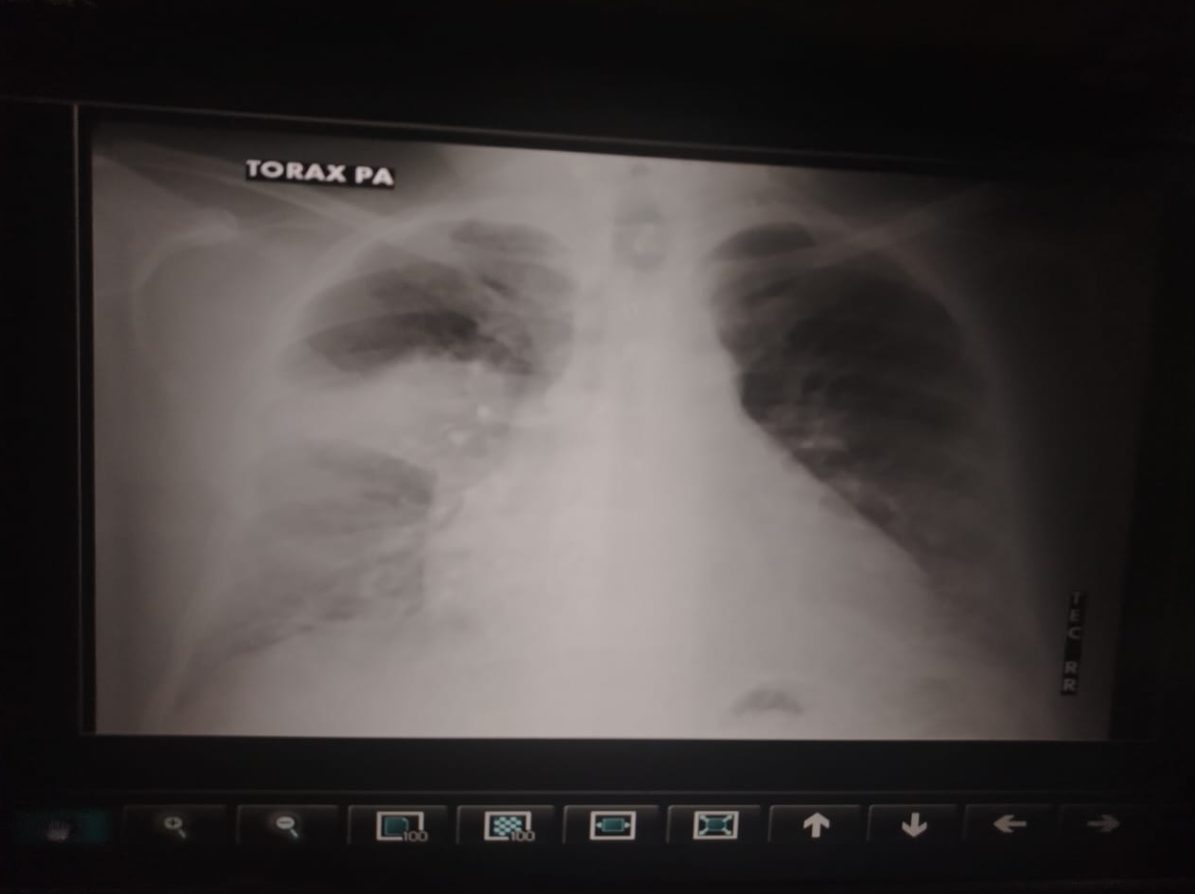

Mielofibrosis: Un tipo de cáncer lento y poco conocido

Publicado el junio 06, 2013 12:42 pmLa mayoría de las personas asocian la palabra cáncer con tumor. Sin embargo, existen varias formas de esta enfermedad que no implican la existencia de […]